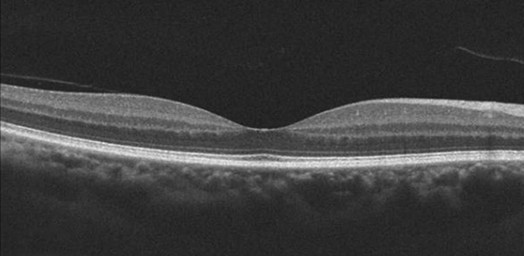

image

Figure 1.2.1 Line scan through the macula.

SD-OCT line scans are a single B-scan composed of generally a higher number of A-scans than the cube scans. This higher sampling density allows higher resolution scans of the retinal tissue to be acquired. In addition, oversampling can be performed to increase signal-noise ratio (Fig. 1.2.1). The Cirrus 5-line raster consists of five horizontal 6 mm lines each scanned four times and averaged. The five lines in the raster can be collapsed to obtain a single line scan that consists of 20 averaged B-scans. The ‘cross-line’ scan of the RT-Vue consists of a horizontal and vertical line scan while the 7-line raster of the Heidelberg also spans a 6 mm × 6 mm area of the macula. Heidelberg can be programmed to oversample a line scan up to 100 times at each point.